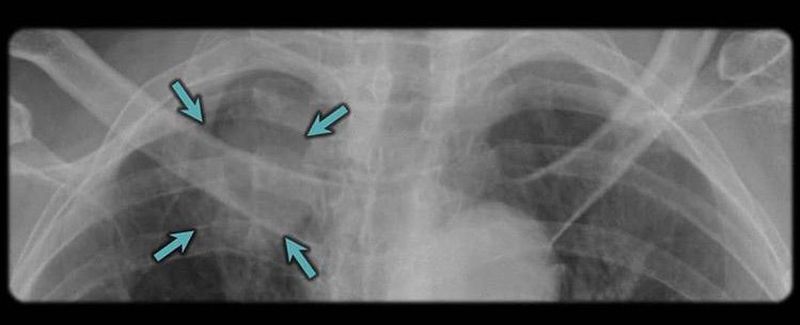

RIGHT APICAL LUNG MASS

heres the answer to my previous post; Right Apical Lung Mass. Remember to compare carefully both left and right side πŸ‘πŸ»